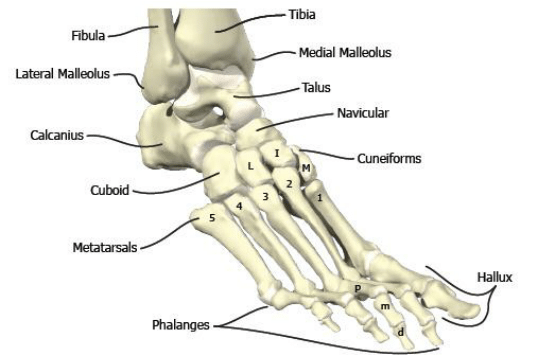

2. Хүний биед байх хамгийн жижигхэн яс чихэнд бий

3. Хүний хөл 26 яснаас бүрддэг